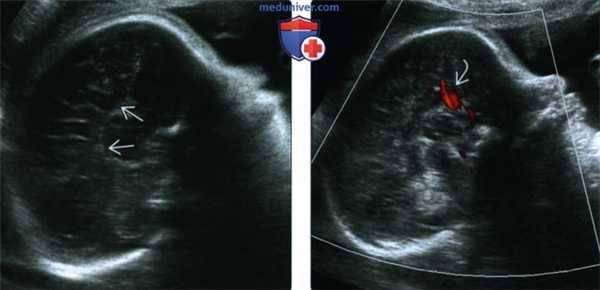

4. УЗИ при дисгенезии мозолистого тела:

• В-режим:

о Корональный срез:

- Отсутствие МТ, форма «бычьей головы» боковых желудочков, их разделение, кольпоцефалия

о Сагиттальный срез:

- Радиально ориентированные извилины, «указывающие» на III желудочек

• Цветное допплеровское картирование:

о Аномальный задний ход ПМА

(Слева) При УЗИ в сагиттальной плоскости выявляется АМТ, отсутствие поясной извилины, видны радиально расположенные извилины, сходящиеся к III желудочку

(Справа) При допплеровском УЗИ обнаруживается патологическое направление околомозолистой артерии, в норме идущей в переднезаднем направлении вдоль поясной извилины. Этот признак может помочь подтвердить диагноз АМТ.